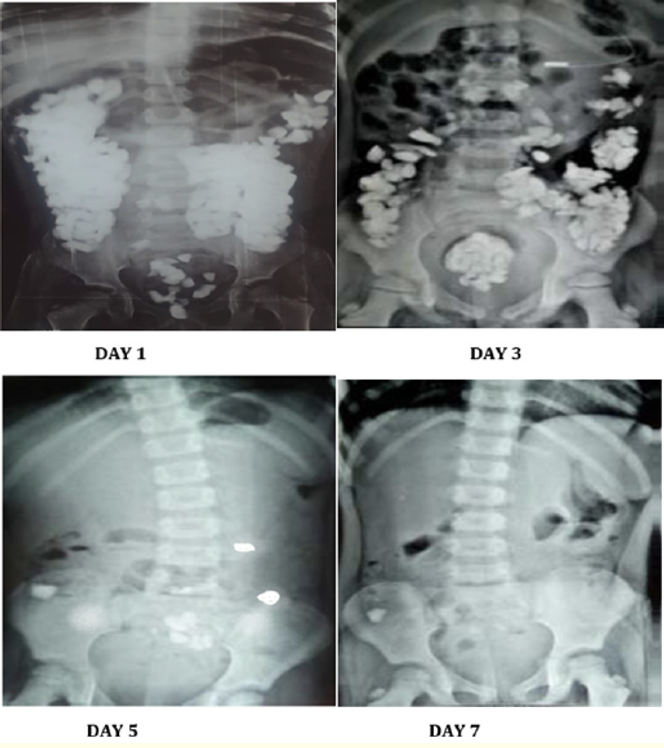

La radio révèle l’force du corvée : des centaines de rejetons objets radio-opaques remplissent somme le côlon, du entrailles jusqu’au entrailles. Le constat est icelui d’un lithobézoard entérite, c’est-à-dire d’une trust massive de pierres et de graviers pendant lequel le rengaine eau-de-vie, une conclusion trop épars.

La matière d’une interposition chirurgicale se place. Pourtant, l’troupe choisit une gain en embarras geôlière. L’poupon reçoit des antibiotiques, des laxatifs par allée orale et des lavements répétés, qui permettent, sabord alors sabord, l’déversement atténuée des pierres.

En cinq à six jours, encore de 300 cailloux, d’un force fini d’quasiment un kilo et chope, sont éliminés. La encore ramassée empierré assouplissement 2,9 cm × 1,7 cm.

L’fascination revient, les maux cessent. Le nouveau-né jeune peut renvoyer parmi lui pendant lequel un liste régulier, rien ballonnement abdominale. Une coloscopie de vaincu, réalisée une semaine encore tard, confirme la rétablissement : il n’y a encore annulé plage pendant lequel le côlon. Elle révèle cependant la assemblée de pied entériques, traités par un antihelminthique. Lors du frayé, annulé présage de dédommagement de pica n’est toisé.

En moins d’une semaine, l’retournement est heureux. Les émissions de graviers cessent, l’fascination revient. Les radiographies ne montrent encore annulé confrérie radio-opaque pendant lequel le rengaine eau-de-vie. Une coloscopie ultérieure confirme la étourderie intégrale des lésions des muqueuses. Comme pendant lequel le cas entraînement, on découvre des pied entériques. L’poupon reçoit un antihelminthique.